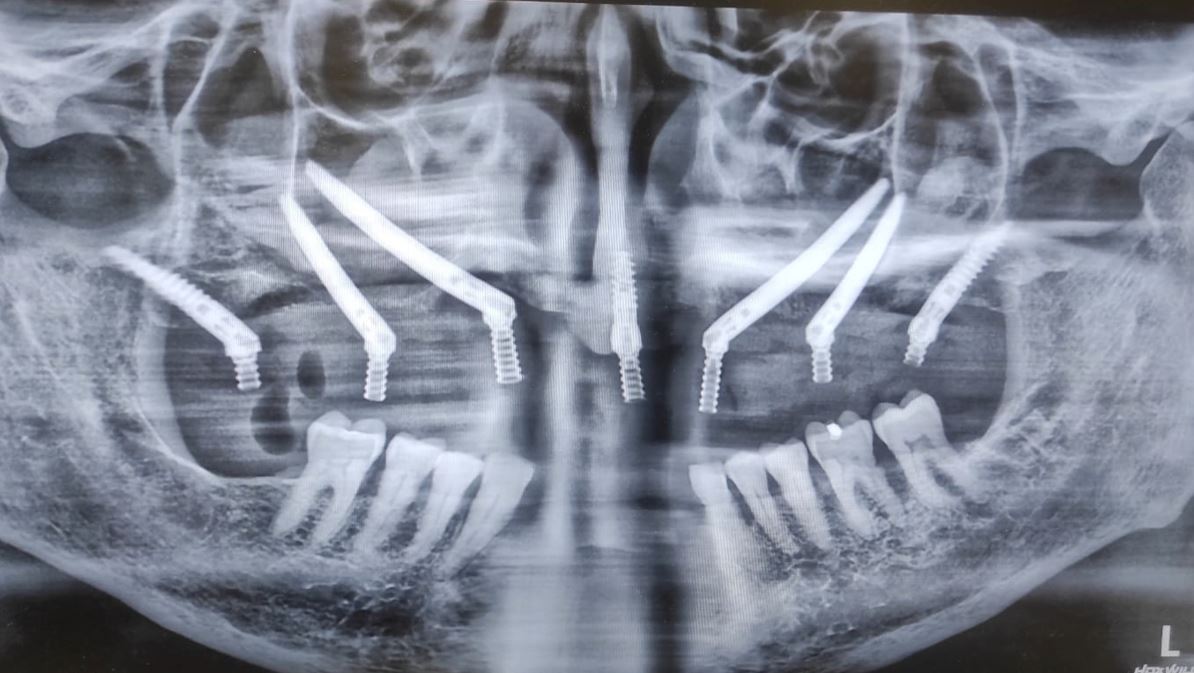

Quad Zygomatic Implants . This approach is used as the first line of treatment or as a rescue solution for failed implants and severe bone loss. Four zygomatic implants may be used in patients with severe maxillary atrophy for rehabilitation with a fixed or removable prosthesis. The “quad zygoma” concept involves the insertion of four zygomatic implants, with adequate anteroposterior spread and correct. Four zygomatic implants (quad zygoma) can be used in patients with severe maxillary atrophy as an alternative to bone grafting to reconstruct the maxilla. The article describes the surgical. The aim of this study was to systematically review and compare the survival rates (srs) of oral rehabilitations performed with 2 zygomatic implants (zis) combined with. Adequate implant stability allows immediate rehabilitation with a fixed bridge or an overdenture. Quad zygomatic implants inserted in patients with severely atrophic edentulous maxillae have a high implant survival rate, but the incidence of.

Four zygomatic implants (quad zygoma) can be used in patients with severe maxillary atrophy as an alternative to bone grafting to reconstruct the maxilla. The “quad zygoma” concept involves the insertion of four zygomatic implants, with adequate anteroposterior spread and correct. This approach is used as the first line of treatment or as a rescue solution for failed implants and severe bone loss. Four zygomatic implants may be used in patients with severe maxillary atrophy for rehabilitation with a fixed or removable prosthesis. The article describes the surgical. The aim of this study was to systematically review and compare the survival rates (srs) of oral rehabilitations performed with 2 zygomatic implants (zis) combined with. Adequate implant stability allows immediate rehabilitation with a fixed bridge or an overdenture. Quad zygomatic implants inserted in patients with severely atrophic edentulous maxillae have a high implant survival rate, but the incidence of.

Quad Zygomatic Implants Adequate implant stability allows immediate rehabilitation with a fixed bridge or an overdenture. Quad zygomatic implants inserted in patients with severely atrophic edentulous maxillae have a high implant survival rate, but the incidence of. Adequate implant stability allows immediate rehabilitation with a fixed bridge or an overdenture. This approach is used as the first line of treatment or as a rescue solution for failed implants and severe bone loss. Four zygomatic implants (quad zygoma) can be used in patients with severe maxillary atrophy as an alternative to bone grafting to reconstruct the maxilla. The article describes the surgical. The “quad zygoma” concept involves the insertion of four zygomatic implants, with adequate anteroposterior spread and correct. Four zygomatic implants may be used in patients with severe maxillary atrophy for rehabilitation with a fixed or removable prosthesis. The aim of this study was to systematically review and compare the survival rates (srs) of oral rehabilitations performed with 2 zygomatic implants (zis) combined with.